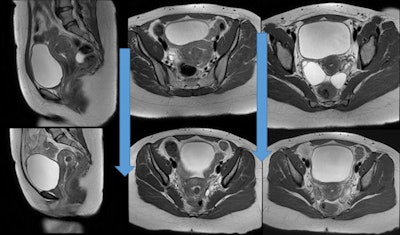

الأدوات التي تستخدم عادة في علاج الأورام الليفية الرحمية بالقثطرة:Robert catheter, microcatheter, and embolization particles.

خلال عملية معالجة الورم الليفي الرحمي بالقثطرة.

تتميز معالجة الأورام الليفية الرحمية عن طريق القثطرة بأنها أبسط و بأن نسبة المشاكل والاختلاطات أقل مقارنة بالاستئصال الجراحي حيث يتم اجراء القسطرة بدون تخدير عام و ياخذ الاجراء 45 دقيقة و تخرج المريضة من المشفى في نفس اليوم.